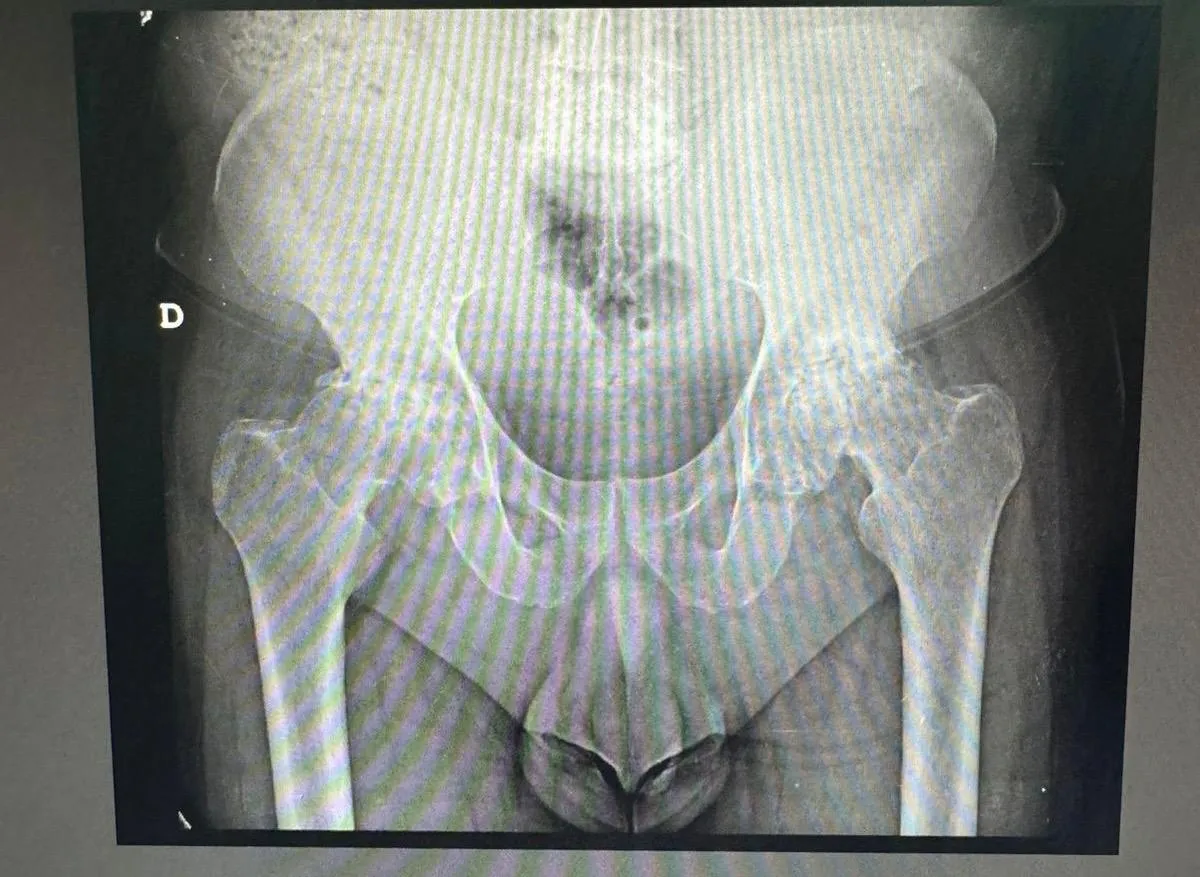

Problemas de cadera — Especialidad principal

La cadera es una de las articulaciones más importantes del cuerpo y una de las áreas de mayor especialización en ortopedia. Los problemas de cadera afectan la capacidad de caminar, sentarse e incluso dormir.

Problemas frecuentes de cadera:

- Artrosis de cadera (coxartrosis) — Desgaste del cartílago articular que causa dolor crónico y rigidez. Es la causa más común de cirugía de reemplazo de cadera.

- Fracturas de cadera — Frecuentes en adultos mayores por caídas. Requieren intervención quirúrgica urgente en la mayoría de casos.

- Necrosis avascular de cabeza femoral — Muerte del tejido óseo por falta de irrigación sanguínea. Puede afectar a pacientes jóvenes.

- Displasia de cadera — Desarrollo anormal de la articulación, presente desde el nacimiento o detectada en la adultez.

- Bursitis y tendinitis de cadera — Inflamación de las bolsas o tendones alrededor de la articulación.

El tratamiento varía según la severidad: desde medicamentos y fisioterapia hasta cirugía de reemplazo articular con técnicas avanzadas como el abordaje anterior bikini, que permite recuperación más rápida y cicatriz mínima.